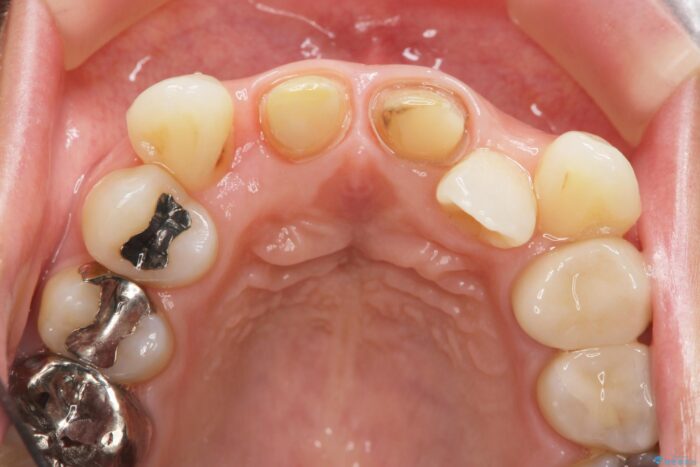

レントゲン検査の結果、以前の根管治療の詰め物が突き出た状態でしたので、まず精密な再治療を行います。同時に、歯磨きがしにくく虫歯の原因になっている右上側切歯を抜歯し、その後、セラミック治療で全体を美しく修復する計画です。

歯磨きがしにくい歯を抜歯することで、今後の虫歯の再発を防ぐ治療計画としました。